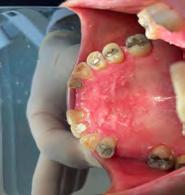

Las Figuras 1-3 muestran las imágenes de la cavidad bucal de la paciente. Se puede observar el deterioro generalizado de la salud bucodental, destacando la higiene dental deficiente, gingivitis, restauraciones dentales desajustadas, exposiciones radiculares, anodoncias parciales y caries radiogénica.

Las Figuras 4-13 son imágenes radiográficas de los dientes de la paciente que presen tan múltiples lesiones periapicales como consecuencia de las necrosis pulpares originadas por la radioterapia. Se realizaron los

tratamientos y retratamientos endodónticos necesarios para preservar los dientes en boca, evitando las exodoncias y por lo tanto minimizando el riesgo de generar osteorradionecrosis.